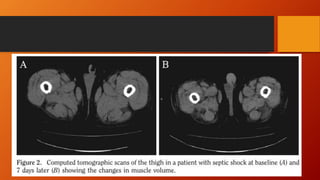

3- Alteração na Função Física

• Fraqueza Muscular adquirida na UTI;

• Alteração na Estrutura e Função muscular;

• Presente em até 80% do pacientes com mais de 7 dias de ventilação mecânica;

• 85-95% irão manter os sintomas de fraqueza por até 5 anos.